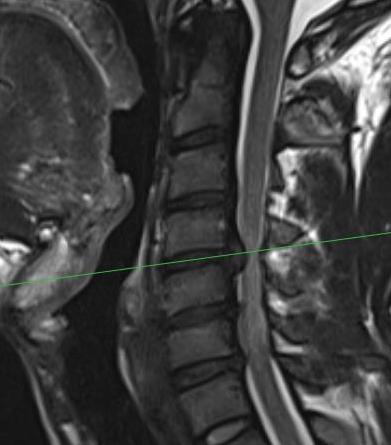

MRI

Paracentral disc

Foraminal disc

CT

May add complementary information to MRI